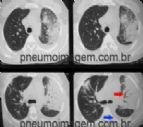

O PNEUMOIMAGEM ALCANÇA 2000 AMIGOS NO FACEBOOK

Alcançamos hoje o número de 2000 amigos no Facebook! Graças a vocês, hoje o PneumoImagem se constitui na maior comunidade em Pneumologia do Facebook no Brasil! O PneumoImagem surgiu há três anos como um site de imagens em Pneumologia, on...